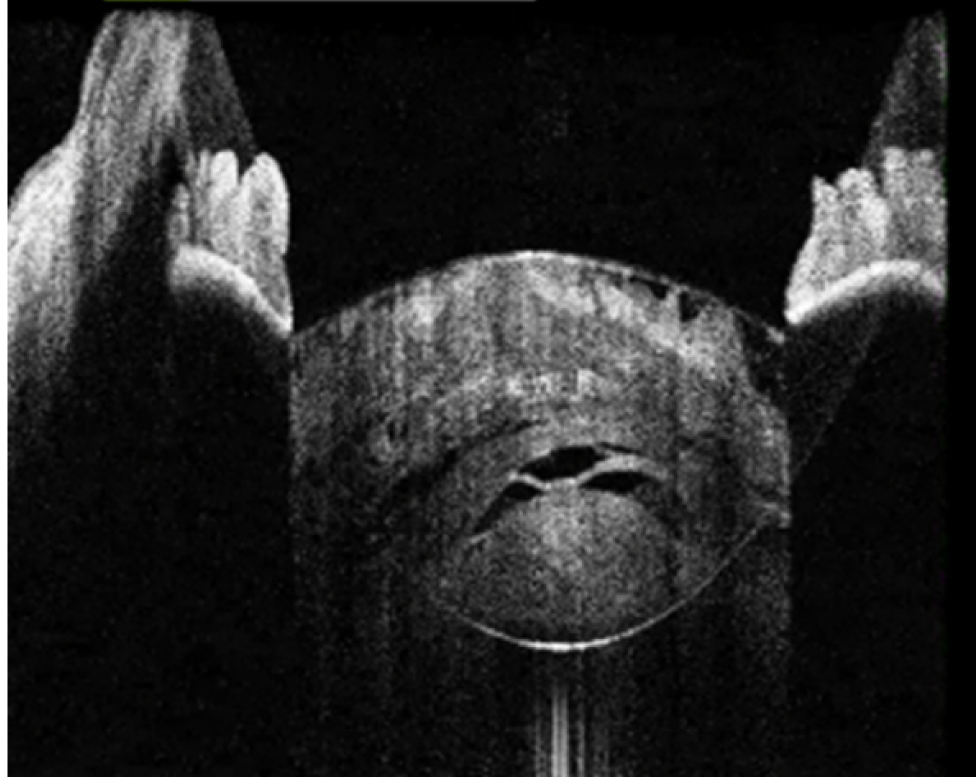

Рис. 2. Тип 2 перезрелой катаракты: непрерывные гиперрефлективные полосы кортикальных волокон, множественные внутрихрусталиковые щели, оводнение хрусталика

Рис. 3. Тип 3 перезрелой катаракты: выпуклая передняя капсула хрусталика, гиперрефлективные полосы набухших кортикальных волокон, внутрихрусталиковые щели, области однородного вида «матового стекла»